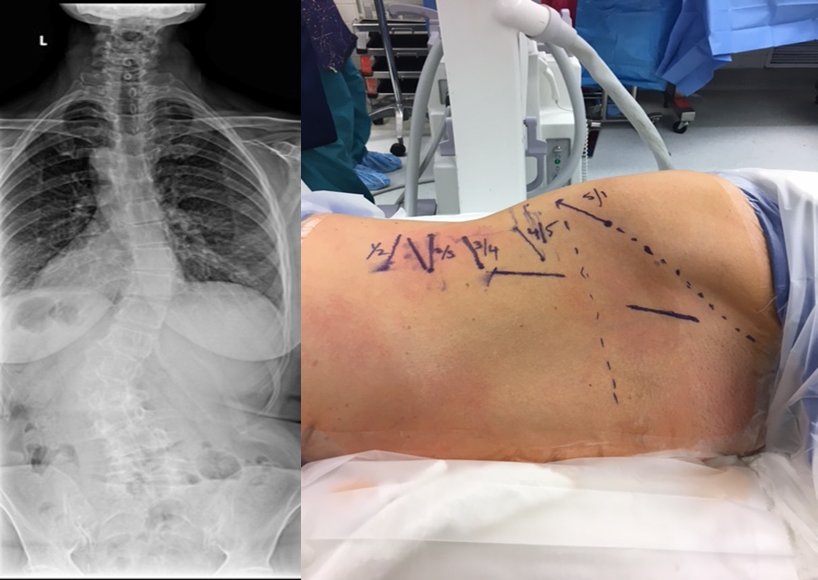

在微创脊柱外科热潮汹涌而至的当下,腰椎退变性疾病的治疗快要达到“无微不至”的程度。那么,就脊柱领域难度超高、风险性巨大的退变性脊柱侧凸而言,医生如何选择开放或微创技术,成为目前脊柱外科的热点之一。

陆军总医院、全军骨科研究所李放教授分析了国内外相关研究,并结合临床经验得出结论:开放手术能够获得更好的矫形和减压效果;微创技术作为脊柱医生手中的新武器,对于一部分畸形较轻的病例,微创技术可以发挥其优势,但要严防特殊并发症;对于畸形严重的病例,微创手术处理存在困难,可谓开放能及微创所不及。他认为,开放和微创技术应该有机结合,重要的是如何去选择适应证,对不同的病例制订个体化方案。